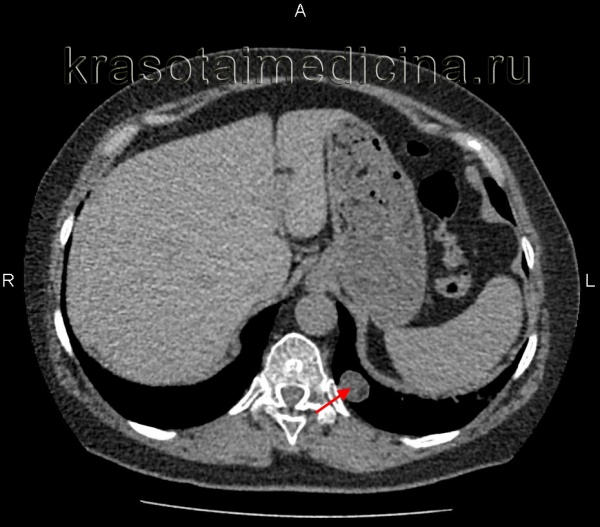

(а) Пациент с костным островком в теле грудного позвонка. При нативной КТ определяется склеротический очаг с четким контуром, который прилежит к корню дуги позвонка и имеет кистевидные края, что является типичным признаком костного островка.